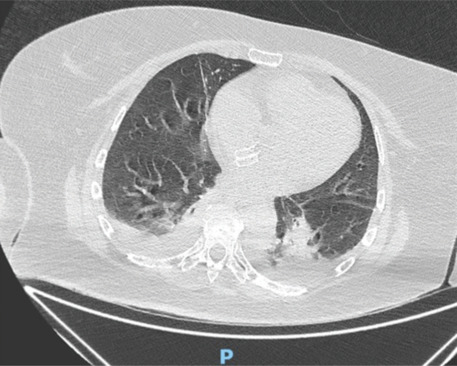

Patent foramen ovale (PFO) is a congenital cardiac defect present in approximately 30% of the general population. While often asymptomatic, it is associated with cryptogenic stroke and paradoxical embolism. Percutaneous closure using atrial septal defect occluder is an effective preventive strategy, but these devices carry a risk of rare complications, including infective endocarditis. Device-associated infective endocarditis is often linked to transient bacteremia following invasive procedures, highlighting the importance of antibiotic prophylaxis. However, the clinical presentation can be variable, requiring a high index of suspicion and advanced imaging for the diagnosis. We describe the case of a 55-year-old woman with hypertension, obesity, and a history of PFO closure with an Amplatzer occluder, who developed infective endocarditis weeks after a dental procedure. She presented with fever, vomiting, and confusion, initially misdiagnosed with encephalitis. Transesophageal echocardiography revealed large filamentous vegetation on the Amplatzer occluder, causing functional mitral regurgitation. Blood cultures identified Staphylococcus aureus and Streptococcus pneumoniae, confirming a mixed bacterial infection. The patient underwent surgical removal of the infected device and mitral valve repair. Postoperatively, she improved significantly and was discharged with a complete course of antibiotics. This case underscores the need for vigilance in patients with intracardiac devices, particularly following bacteremia-inducing procedures. Early diagnosis using echocardiography and prompt surgical intervention are essential to managing device-related infective endocarditis. While antibiotic prophylaxis may reduce the risk of bacteremia-related infections, the lack of high-quality evidence necessitates further research to guide preventive strategies. Multidisciplinary care and strict adherence to diagnostic and therapeutic protocols remain pivotal to improving patient outcomes.